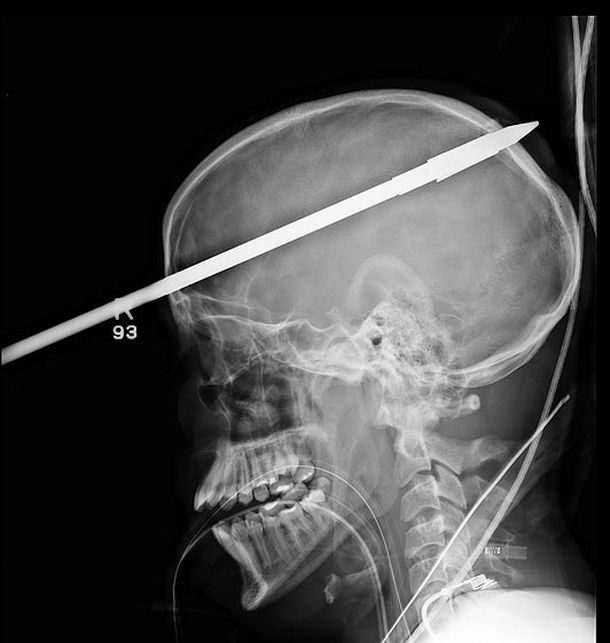

Radiografía del adolescente que recibió un arponazo

Un chico de 16 años fue herido con un arpón que le traspasó el cráneo y el cerebro.

Según su amigo, un muchacho de 15 años cuyo nombre no trascendió, López disparó el arpón accidentalmente y la vara dio un centímetro por encima de su ojo derecho y quedó alojada de ese lado del cerebro.

A su llegada al hospital, López no paraba de gritar en español, pero enseguida perdió la conciencia y los médicos lo introdujeron al quirófano, donde le extirparon el arpón de 90 centímetros de largo.

"Es un milagro que el arpón no afectó a las venas dentro del cerebro", indicó el cirujano George García en una conferencia de prensa realizada en el centro médico el lunes pasado. Por fortuna para López, el arpón tampoco comprometió su centro del habla o el de la personalidad.